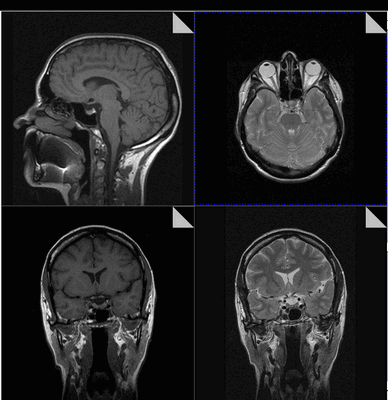

Магнитно-резонансная томография обеспечивает сканирование области турецкого седла в трех взаимно перпендикулярных проекциях. Послойные монохромные снимки детализируют состояние анатомических структур зоны интереса, показывая малейшие изменения формы, размера, строения рассматриваемого объекта.

МРТ гипофиза до и после операции по удалению макроаденомы гипофиза

Чаще всего исследование проводится для диагностирования аденомы гипофиза и определения ее величины: микроаденомы (до 10 мм), макроаденомы (10—30 мм) и гигантской аденомы (более 30 мм). Также с его помощью обнаруживаются неоднородности структуры, асимметрия границ, изменения положения воронки гипофиза и ее структуры, а также деформации окружающих костных тканей.

МРТ гипофиза. На МР-томограмме определяется гигантское образование неоднородной структуры (обведено) — макроаденома гипофиза.